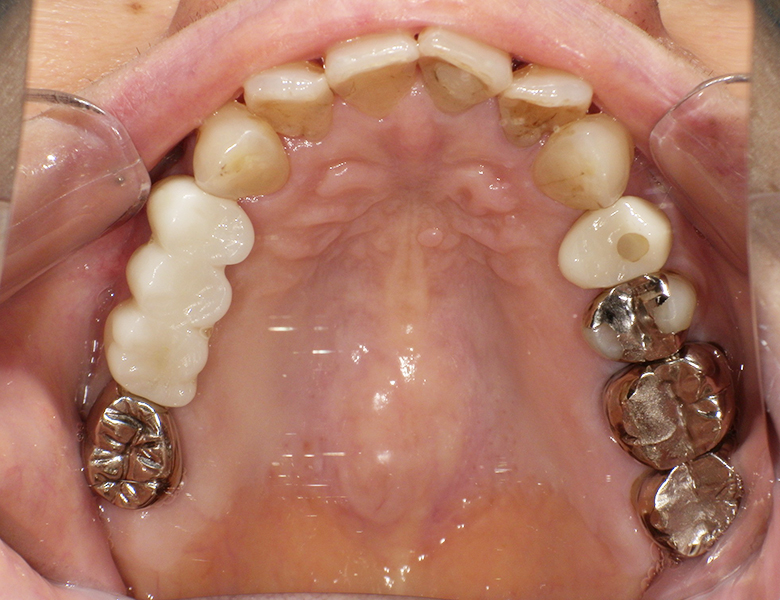

治療後 ![]() |

14・16部位にインプラントを埋入し、それを支台としてジルコニアブリッジを装着する治療をご提案しました。強度に優れ、見た目も自然なジルコニアを使用することで、長期的な安定性と審美性の両立を目指しました。 |

術後はしっかり噛めるようになり、食事の不安が解消されました。ブリッジ部も自然な色調で、周囲の歯と調和した仕上がりとなっています。現在はメンテナンスで良好な状態を維持されています。 |